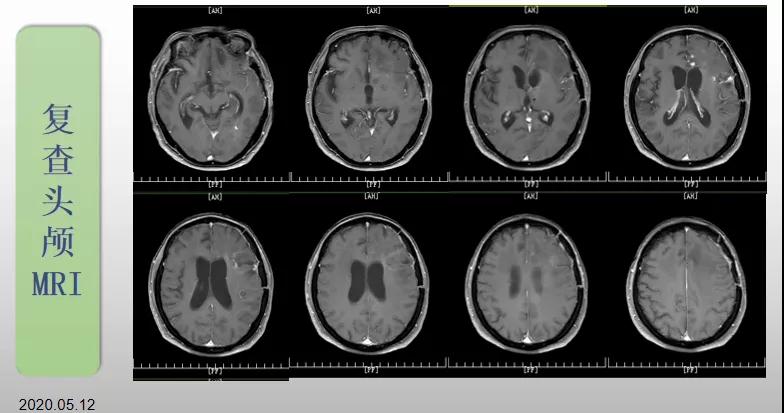

綜合治療 電場治療助70歲患者回歸正常生活

70歲的郝女士去年曾在外院查出“左額島葉”膠質(zhì)母細胞瘤(WHO Ⅳ級),并做了左側(cè)額島葉占位性病變切除術(shù)。術(shù)后進行了同步放化療。由于治療條件有限,郝女士慕名來到我院就診。賀世明主任率領(lǐng)醫(yī)護團隊立即為郝女士進行了全面的檢查,決定為其進行綜合治療 電場治療。經(jīng)過三個多月的綜合治療,患者復查頭顱MRI病變較前明顯縮小。出院時,郝女士神志清醒,睡眠飲食正常,說話很流利。“我是躺著進來的,現(xiàn)在不用人攙扶,自己就可以走出病房了。”郝女士拉著醫(yī)護人員的手說。